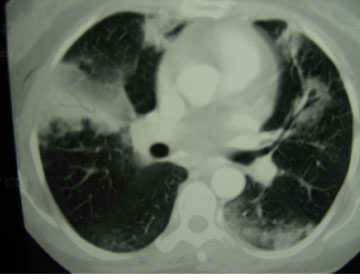

1) Dreifðar lungnablöðruþéttingar

Þetta er algengasta mynd trefjavefslungnabólgu með dreifðum þéttingum af lungnablöðrugerð (sjá mynd IV). Þéttingar eru oft útlægar og beggja vegna. Stærð þéttinganna getur verið nokkuð breytileg, allt frá nokkrum sentimetrum yfir í heilt lungnablað og stundum flakkandi (migratory) (12). Að sama skapi getur þéttleiki íferðanna verið nokkuð misjafn, allt frá hélun (ground glass) yfir í þéttingu með loftberkjukorti (air bronchogram). Algengt er að tölvusneiðmynd leiði í ljós fjölda þéttinga sem ekki sjást með hefðbundinni rönt-genmynd. Dæmi um sjúkdóma með svipað mynstur þéttinga eru langvinn eósínófíl lungnabólga, hægt vaxandi eitlakrabbamein og lungnakrabbamein, ekki síst af berkju- og lungnablöðru (bronchoalveolar) gerð (12, 33).

Mynd IV. a) Röntgenmynd af lungum og b) tölvusneiðmynd af lungum sýna útlægar og dreifðar þéttingar beggja vegna af lungnablöðrugerð (12). (Birt með leyfi European Respiratory Journal.)